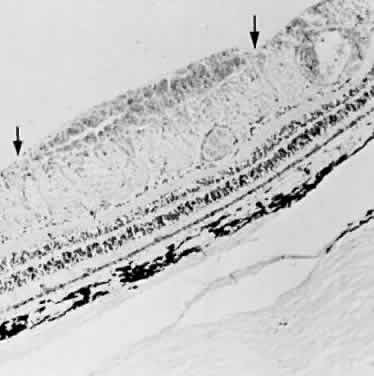

beneath the retinal pigment epithelium seems much darker. A hemorrhage in the nerve fiber layer (Fig. 11A) dissects along the plane of the layer parallel to the orientation of

the internal limiting membrane (see Fig. 11B). A hemorrhage located between the retinal pigment epithelium and Bruch's

membrane also spreads in a plane parallel to the orientation

of the membrane (Fig. 12). However, its extent is limited by the adhesion of the pigment epithelium

to Bruch's membrane, in contrast to a nerve fiber layer hemorrhage, where

no such delineating structure is present. Therefore, a fresh

nerve fiber layer hemorrhage appears bright red and has feathery

borders, whereas a subpigment epithelial hemorrhage appears brown-black

and has sharp borders (Fig. 13).  Fig. 11. A. Section of retina with hemorrhage in the nerve fiber layer (between the two large arrows). Notice that the limits of the hemorrhage are not clearly defined, since

scattered red blood cells can be seen to the right of the right-hand

large arrow. This histologic picture corresponds to a clinically observed

fame-shaped hemorrhage with an indistinct border. The detached

posterior hyaloid is marked by four small arrows. B. Fundus photograph of nerve fiber layer hemorrhage. They are oriented parallel

to the plane of the internal limiting membrane. Because of their

dispersal within the ganglion cell layer, the borders are “feathery” (flame

shaped). Fig. 11. A. Section of retina with hemorrhage in the nerve fiber layer (between the two large arrows). Notice that the limits of the hemorrhage are not clearly defined, since

scattered red blood cells can be seen to the right of the right-hand

large arrow. This histologic picture corresponds to a clinically observed

fame-shaped hemorrhage with an indistinct border. The detached

posterior hyaloid is marked by four small arrows. B. Fundus photograph of nerve fiber layer hemorrhage. They are oriented parallel

to the plane of the internal limiting membrane. Because of their

dispersal within the ganglion cell layer, the borders are “feathery” (flame

shaped).